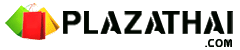

ล่าสุด วันที่ 6 พฤศจิกายน 2563 เฟซบุ๊ก Infectious ง่ายนิดเดียว ได้โพสต์ภาพฟิล์มเอกซเรย์ปอดเด็กที่ติดเชื้อไวรัส RSV 10 คน ที่เข้ารับการรักษาที่โรงพยาบาล โดยได้รับการวินิจฉัยว่ามีอาการหลอดลมอักเสบ ปอดอักเสบ โดยฝ้าสีขาวคือตำแหน่งทีติดเชื้อ สีดำคือปอดปกติ พร้อมระบุข้อเท็จจริงของ RSV ดังนี้